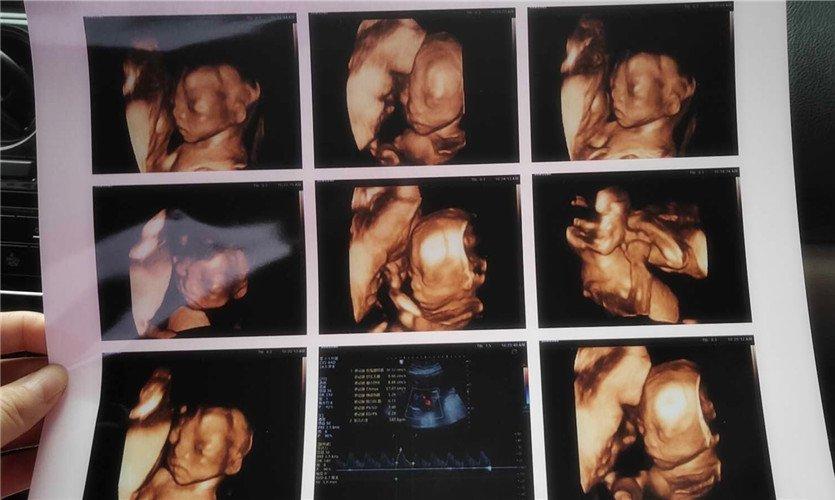

做四维彩超宝宝表现各异,医生暗示有趣,检查很重要是四维彩超。 很多人希望通过四维彩超可以提前看到宝宝的样子,以及在妈妈肚子里的“动态”情况。当然,更重要的是为了通过此项检查来确定胎儿的健康情况。 不少准妈妈会听到过来人的提醒,说做四维彩超时,如果宝宝配合就很顺利,如果宝宝不配合甚至要去几次才能够做完这项检查...

做完四维彩超孕妇被宝宝丑哭,宝宝真颜值还得看父母四维照上孩子的相貌,跟宝宝出生后的样子不是完全相同的。 四维照上看到宝宝的样子有些丑,其实是正常的。 做四维彩超虽然可以看到宝宝的... 特别是以下几个方面更容易遗传到。 眼睛 父母如果有一方眼睛很大,很可能会生出大眼睛的宝宝。父母有一方是双眼皮,宝宝有可能会是双眼皮...

孕妈为做四维趴大厅座椅调整胎儿体位,四维这样做,才能轻松过关我反复做了9次四维彩超才最终完成检查。” “在进行胎儿心脏彩超时,我被医生赶出B超室多达5次,尝试了爬楼梯和吃东西等方法都未能让宝宝配合。然而,当我最终选择静静坐着不动时,宝宝竟然出奇地配合了检查。” “在进行四维彩超时,我花费了整整一天半的...